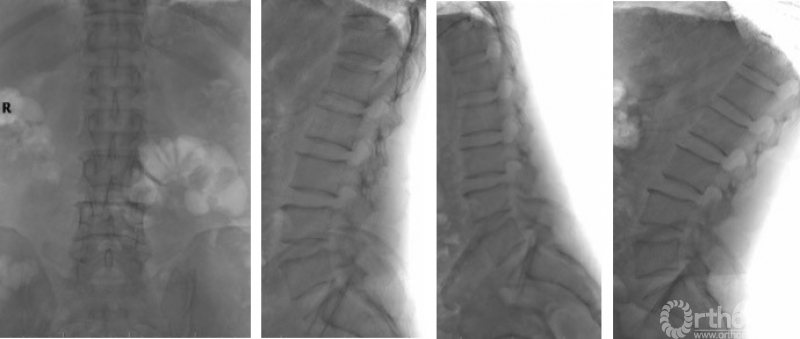

一般情况:患者,男,56岁,主因“间断腰痛30年,加重伴左下肢间歇性跛行2月余”入院。

患者30年前无明显诱因出现下腰部疼痛,2月前无明显诱因出现左臀部、大腿外侧、小腿外侧至足背外侧行走约200米后疼痛,弯腰休息后缓解,MRI提示“腰椎管狭窄症”,入院行2周保守对症治疗后疼痛缓解出院。1个月后,患者再次就诊于门诊,此次行走约50m即出现左下肢放射痛,位置同前。

查体:视触动量等检查均无明显阳性体征,病理征、四肢腱反射等神经查体均正常。核磁提示:L3/4、L4/5椎管狭窄,L3/4纤维环HIZ,L4/5左侧隐窝狭窄,L5/S1纤维环HIZ。腰椎稳定性可。(图7)

入院诊断:腰椎管狭窄症(L3/4、L4/5);高血压2级。

图7

图8

困惑:L3-5节段椎管狭窄,纤维环存在HIZ,腰痛来源不明。患者症状为狭窄,查体未诱发出明显阳性体征,无法精确定位责任节段。为保证手术效果,开放手术需解除L3-5两个节段狭窄,创伤相对较大。患者对开放手术抵触,要求微创治疗。

解决方案(图9):

① 腰椎间盘造影L3/4:注射2.5ml造影剂后,造影剂沿HIZ向椎管内渗漏,但未诱发下腰痛或放射痛;

② 腰椎间盘造影L4/5:注射2.5ml造影剂后,造影剂在间盘内分层,诱发出下腰痛,复制出轻度的左下肢放射痛;

③ L5出口根造影:穿刺针刺激出口根,复制出明显相同部位的放射痛,局部注射造影剂0.5ml[2],沿出口根走行显影,局部注射局麻药+类固醇封闭,患者疼痛缓解。下床行走约200m后,未出现间歇性跛行症状。患者要求暂保守治疗出院。

④ 因患者应用局麻及类固醇止痛、缓解炎症,验证性试验同时,具有治疗作用,如患者症状复现,可择期行L4/5节段内镜下单侧入路双侧减压术或单节段MIS-TLIF进行椎管减压。